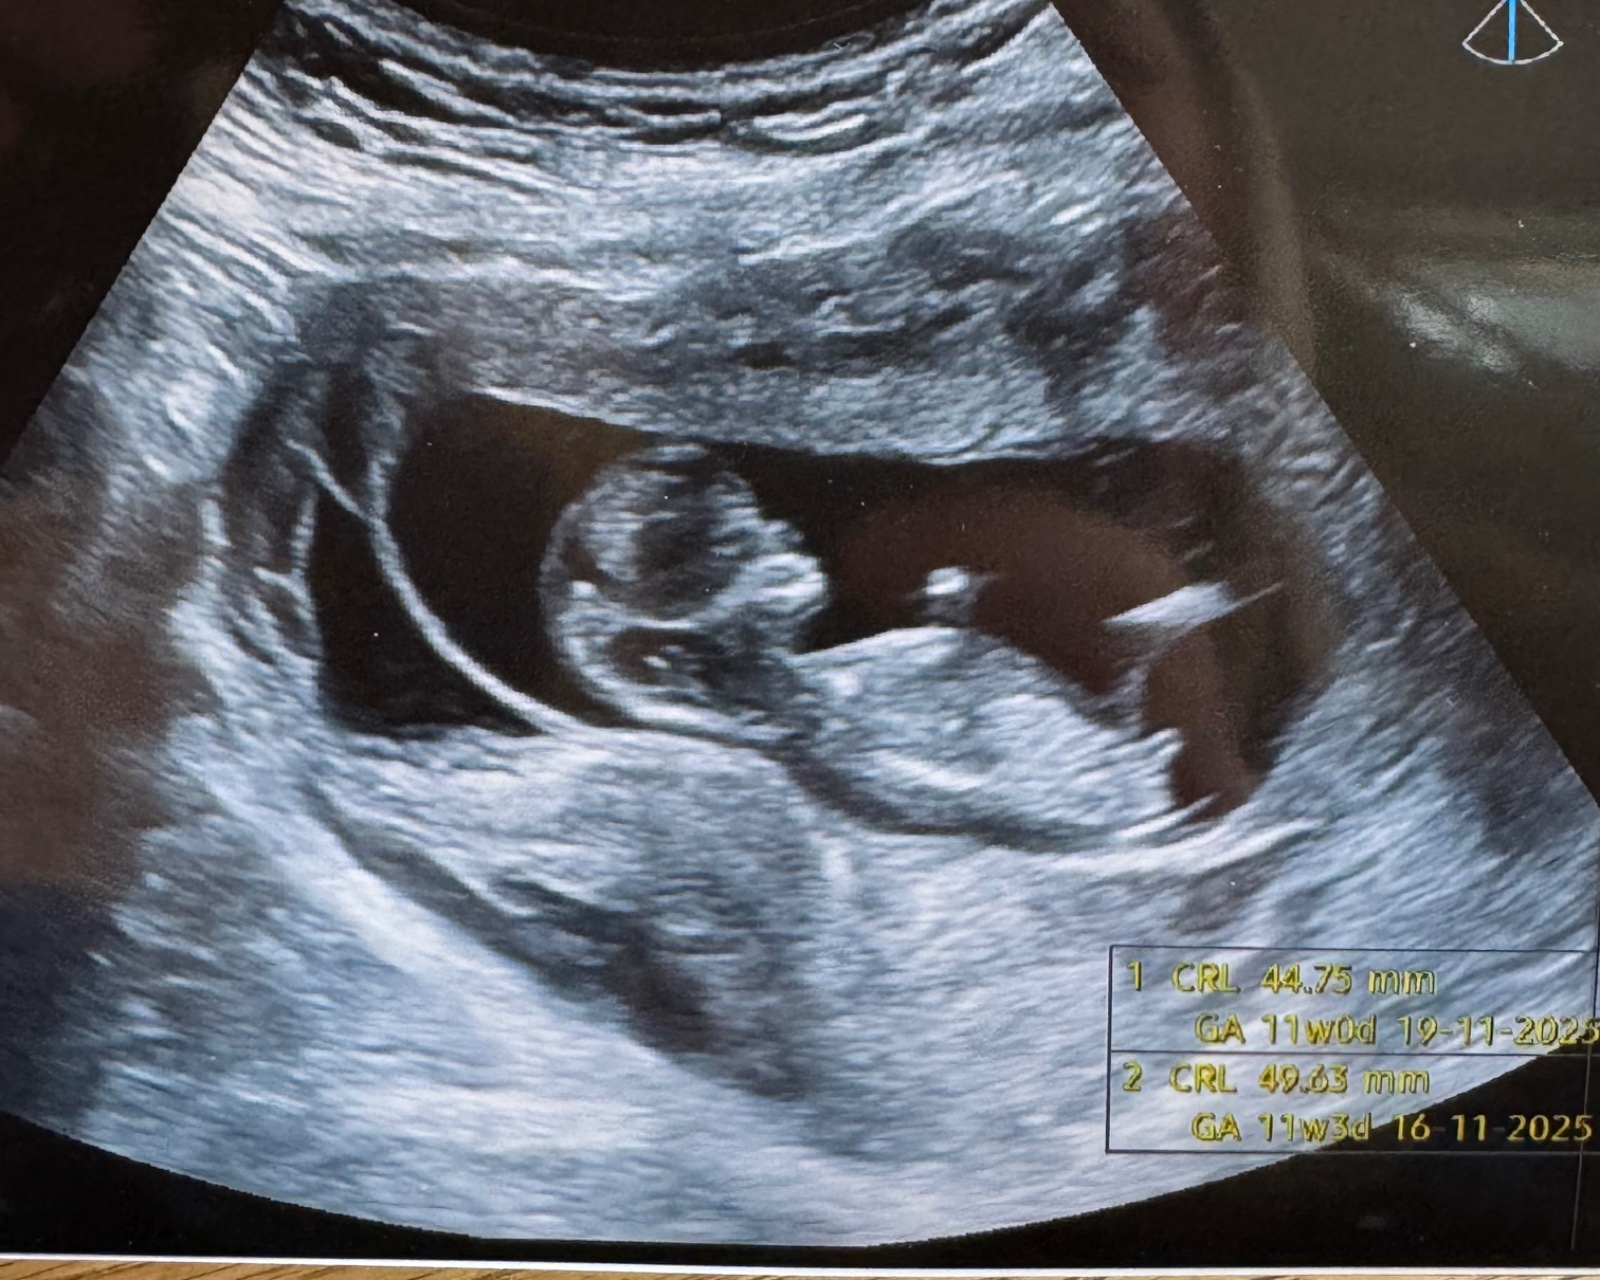

je možné poznat pohlaví?

omlouvám se, ale posuzovat pohlaví z jedné či několika fotografií v prvním trimestru je poměrně nepřesné a u velké části plodů nelze vůbec. Nenahradí to vyšetření v reálném čase a i to má velké limitace. Vydržte do pozdějších fází, kdy to lze v naprosté většině případů odhadovat téměř stoprocentně.